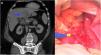

Caso 2. Varón de 44 años con clínica de dolor abdominal difuso de un mes de evolución, que consulta por reagudización del mismo y leucocitosis (18.500 mil/mm3). En la TAC se observa en el lóbulo hepático izquierdo un cuerpo extraño lineal de densidad calcio de 4cm, adyacente a una colección intraparenquimatosa de 5cm de diámetro mayor, sugestiva de absceso hepático (fig. 2a); asimismo presenta edema alrededor de la segunda porción duodenal, con posible zona de perforación. Se decide iniciar tratamiento conservador con antibioterapia empírica, con buena evolución y siendo alta al octavo día.

a) Corte axial de la TAC, donde se observa absceso intrahepático en lóbulo hepático izquierdo señalado con la flecha azul. b) Imagen intraoperatoria durante la extracción de espina de pescado del hígado. Los colores de la figura solo pueden apreciarse en la versión electrónica del artículo.

Se decide posteriormente cirugía electiva; tras laparotomía subcostal bilateral, se encuentra plastrón inflamatorio en curvatura menor gástrica. Se lleva a cabo drenaje del absceso, cierre de la perforación en antro gástrico y retirada de la espina de pescado (fig. 2b). El paciente es dado de alta al quinto día, sin complicaciones ni recurrencia posterior.